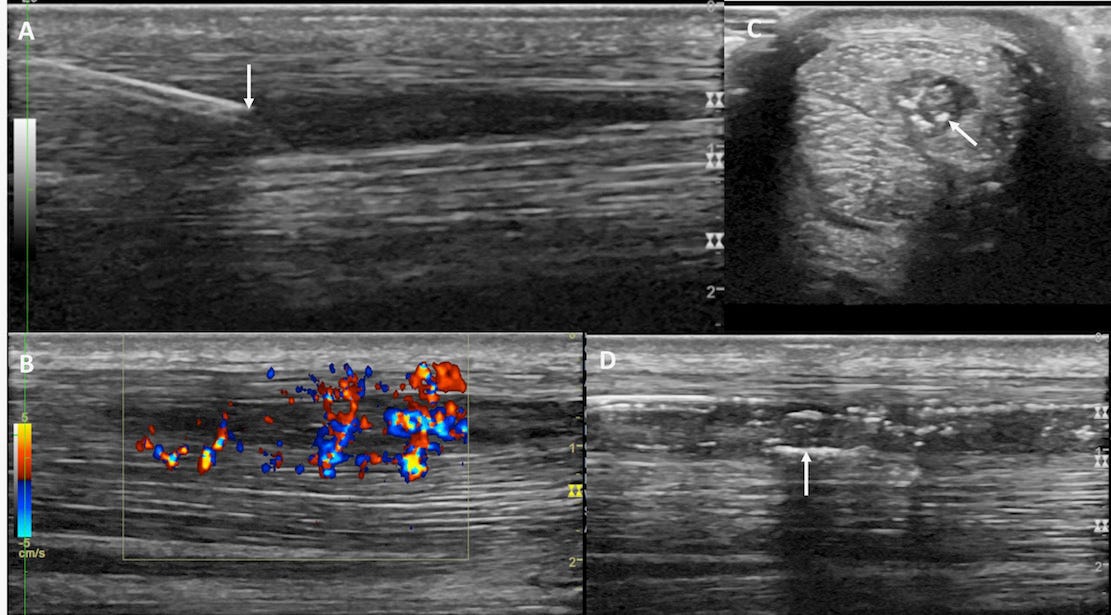

· Ultrasound tissue characterisation of the superficial digital flexor tendons in juvenile Thoroughbred racehorses during early race training suggests that there are short-term changes with the onset of training, although it is not possible to know, at this stage, whether these changes have any relationship to the risk of injury.

· The use of sonoelastography to assess the recovery of stiffness after equine superficial digital flexor tendon injuries: A preliminary prospective longitudinal study of the healing process. This study potentially presents another way to monitor tendon healing and predict outcomes.

· Ultrasonographic-based predictive factors influencing successful return to racing after superficial digital flexor tendon injuries in flat racehorses: A retrospective cohort study in 469 Thoroughbred racehorses in Hong Kong: This work confirms that lesion size was predictive of outcome.

· Retrospective analysis of oblique and straight distal sesamoidean ligament desmitis in 52 horses includes a technique for optimising ultrasonography for imaging oblique DSL injuries.